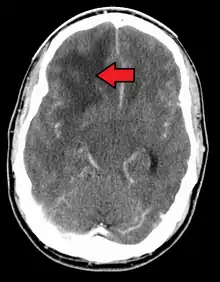

![]() | |

| Coronal MRI (viewed from the back of the head) with contrast of a glioblastoma in a 15 year old boy | |